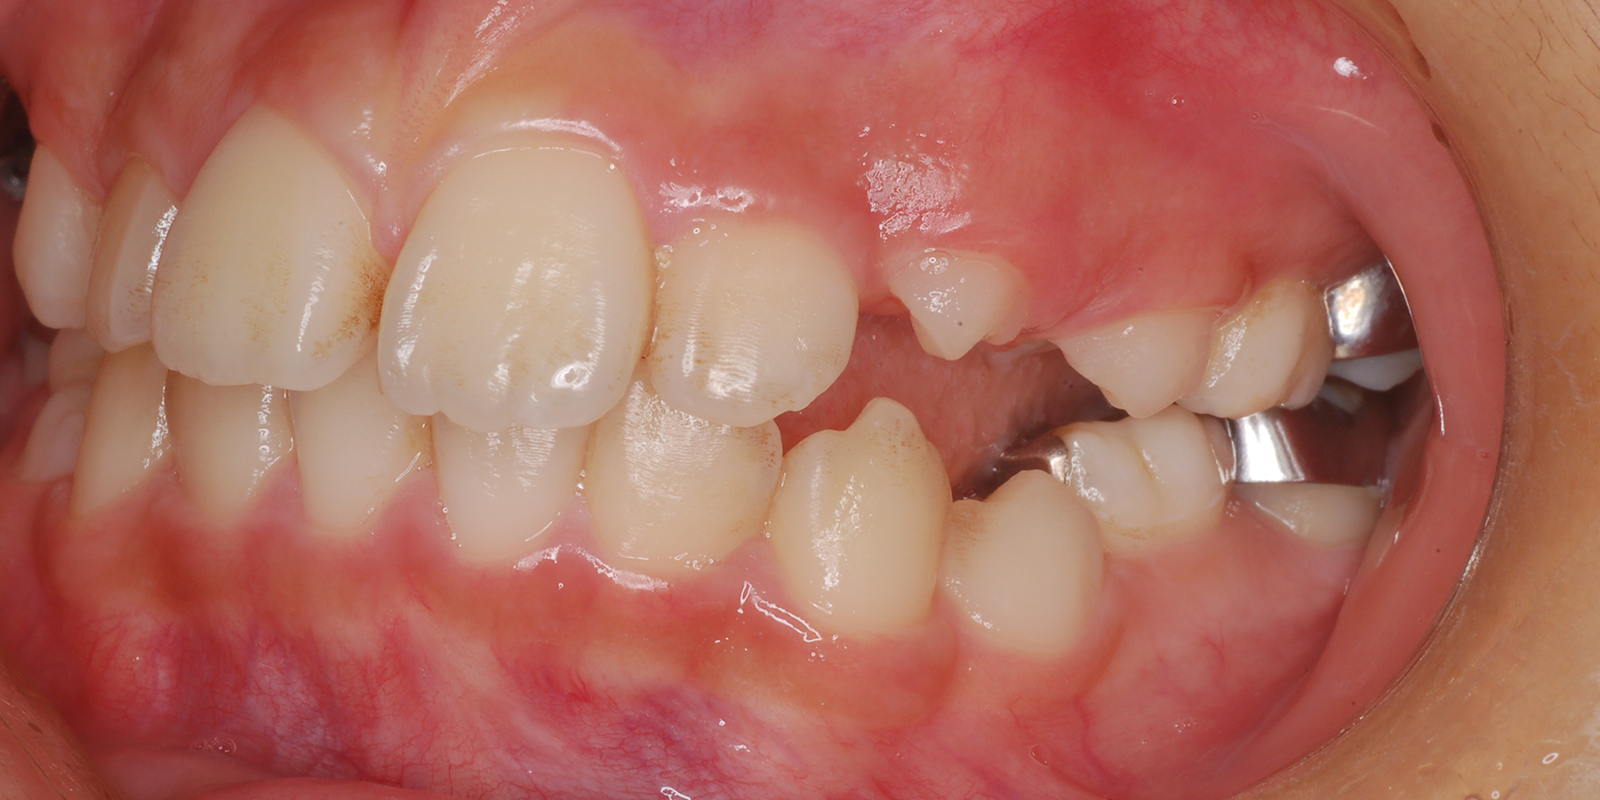

MIX反対咬合

術前

術後

| 主訴 | 受け口 |

| 診断 | アングルⅢ級反対咬合 |

| 初診時年齢 | 8歳1か月 |

| 装置 | 舌側弧線装置 |

| 抜歯・非抜歯 | 非抜歯 |

| 治療期間 | 2年7か月 |

| 通院回数 | 20回 |

| 治療費 | 25万円 矯正歯科治療は公的医療保険の適用外の自費(自由)診療となります |

| 治療のリスク | ・ばねが口から飛び出してくることがあります ・装着当初話しにくい場合があります |